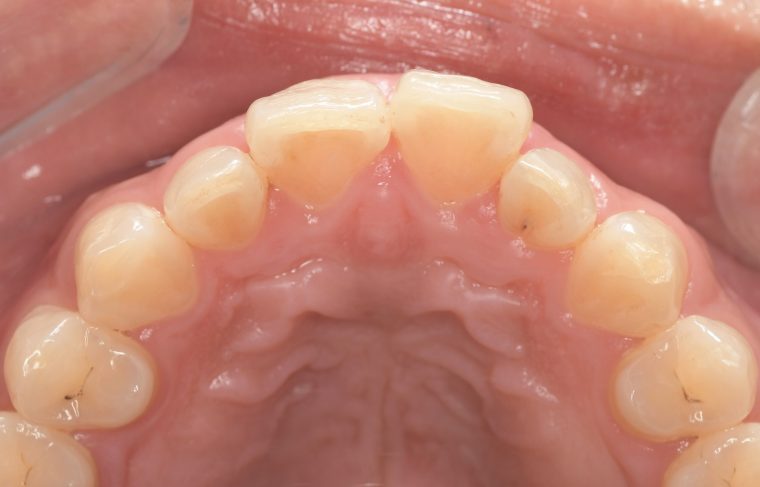

Before

After

基本情報

| 年齢・性別 | 30代・男性 |

| 主訴 | 歯石を取りたい |

| 治療内容 | 超音波スケーラーでの歯石除去 |

| 治療期間 | 60分 |

| 治療費 | 初診料を含め約4,500円 |

| リスク・副作用 | 歯ぐきに違和感や痛みを覚える場合がある。 1週間程度、歯を磨くといつもより出血することがある。 腫れていた歯ぐきが引き締まることで歯ぐきが下がった様に見える。 歯ぐきが下がることで歯がみしやすくなることがある。 一時的に歯の動揺(ゆれ)が増す場合がある。 |